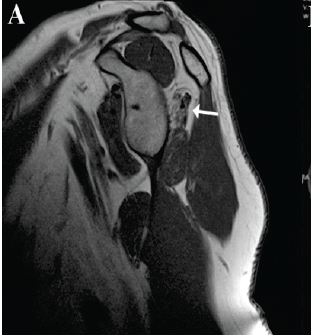

Irreparable Isolated Infraspinatus Musculotendinous Lesion Treated With Lower Trapezius Tendon Transfer: Case Report

Bo Taek Kim , Luis Alfredo Miranda , Jean David Werthel , Justine Fleurette , Chang Hee Baek , Jean Kany